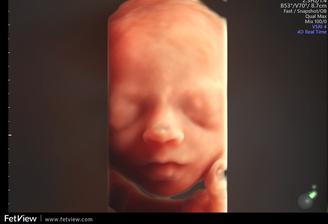

Nase tretie kuriatko😘😙💜